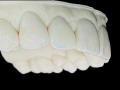

Technika Injection Flowable i technika stempla. Odbudowa…

Rekonstrukcja protetyczna utraconej estetyki uśmiechu